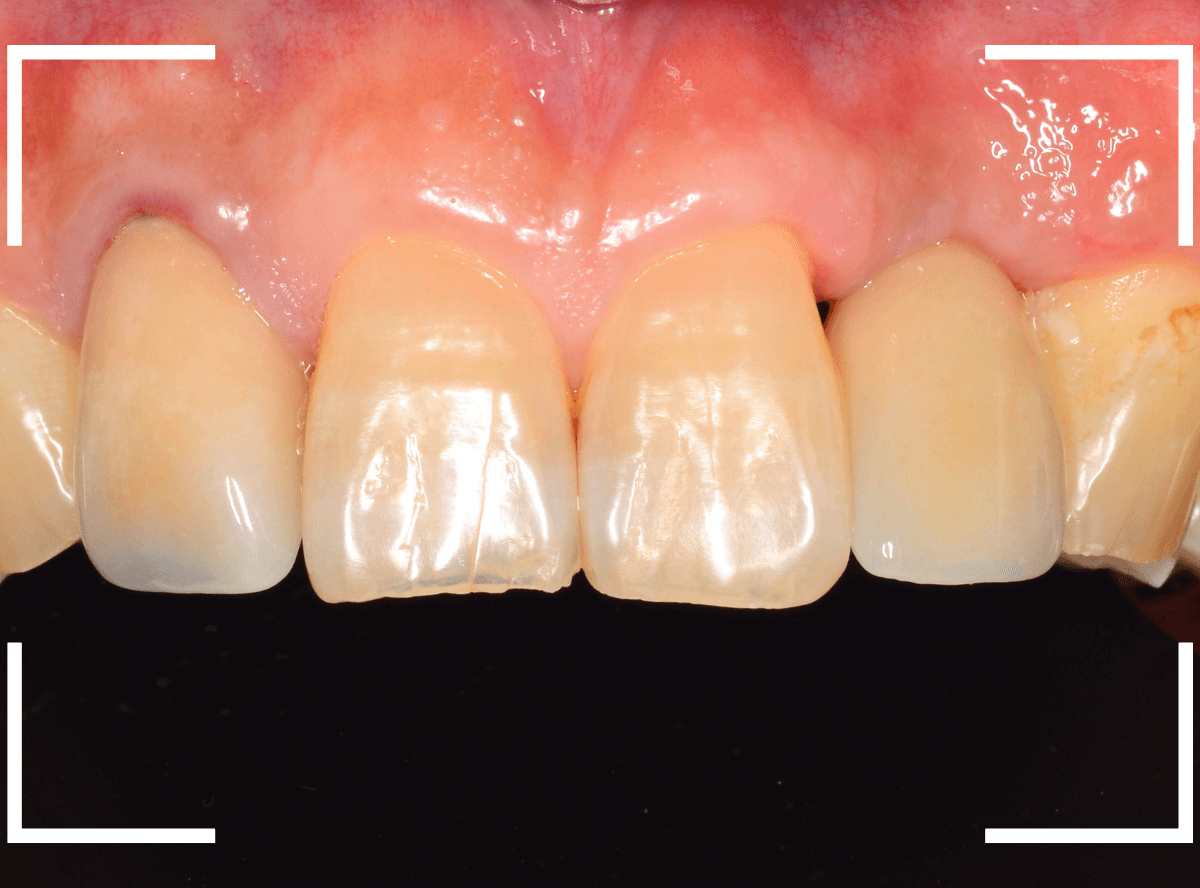

インプラントset後の状況です。

審美的にも、満足いただける仕上がりになりましたが、現在の状況を維持するために治療後の定期メンテナンスが不可欠になります(インプラントに限りませんが)。